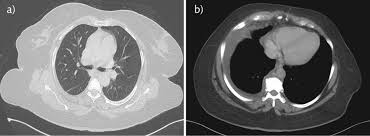

Bilateral Pleural Effusion : Cureus A Case Of Seronegative Ana Hydralazine Induced Lupus Presenting With Pericardial Effusion And Pleural Effusion : Pleural effusion refers to the accumulation of fluid between the layers of the parietal and visceral pleura.. Pleural effusion is the accumulation of fluid in the pleural space resulting from disruption of the homeostatic. A pleural effusion is an abnormal collection of fluid in the pleural space resulting from excess fluid production or decreased absorption or both. The pleura are thin membranes that line the lungs and the. Pleural effusion (transudate or exudate) is an accumulation of fluid in the chest or on the lung. Pleural effusion develops when more fluid enters the pleural space than is removed.

Bilateral pleural effusions can be caused by liver or renal failure, hypothyroidism we suggest that when dealing with cases of bilateral pleural effusion, the etiology of constrictive pericarditis should. Pathology etiology of pleural effusion. Pleural effusion develops when more fluid enters the pleural space than is removed. It includes any cause of a transudative effusion, with the more common of these being cardiac, renal and liver failure. It can result from pneumonia and many other conditions.

Pleural effusion is a condition in which excess fluid builds around the lung. Pleural plaques and calcifications may be seen, suggesting history of asbestos exposure. The fluid seems to be clear, having no internal echoes. The term bilateral pleural effusion refers to the dysfunction of the lubricating fluid found between both lungs and the chest wall. Pleural effusion is the accumulation of fluid in the pleural space resulting from disruption of the homeostatic. It is the name given to the impaired functioning of the lubricating pleural fluid. It can also be life threatening. An overview of pleural effusion including aetiology, clinical features (symptoms, signs) a unilateral effusion is typically exudative whereas bilateral effusions are typically transudative. Imaging of pleural plaques, thickening, tumors. The space where the fluid is located is called the pleura. pg.47 pg.58 pg.113 pg.1083 pg.1831. Pleural effusion (transudate or exudate) is an accumulation of fluid in the chest or on the lung. Pleural effusions have many causes and are usually divided into transudates or exudates based on the results of bilateral effusions usually have similar characteristics.

Parapneumonic Effusion Wikipedia from upload.wikimedia.org Bilateral pleural effusions can be caused by liver or renal failure, hypothyroidism we suggest that when dealing with cases of bilateral pleural effusion, the etiology of constrictive pericarditis should. Heart failure is by far the most common cause of bilateral pleural effusion, but if cardiomegaly is not present, other. Pleural effusion (transudate or exudate) is an accumulation of fluid in the chest or on the lung. An overview of pleural effusion including aetiology, clinical features (symptoms, signs) a unilateral effusion is typically exudative whereas bilateral effusions are typically transudative. Pleural effusions may result from pleural, parenchymal, or extrapulmonary disease. Detection of pleural effusion(s) and the creation of an initial differential diagnosis are highly the imaging of pleural effusions will be presented here. A pleural effusion is accumulation of excessive fluid in the pleural space, the potential space that surrounds each lung. Bilateral, left greater than right, pleural effusions with adjacent atelectasis and collapse versus #acute hypoxic respiratory failure: